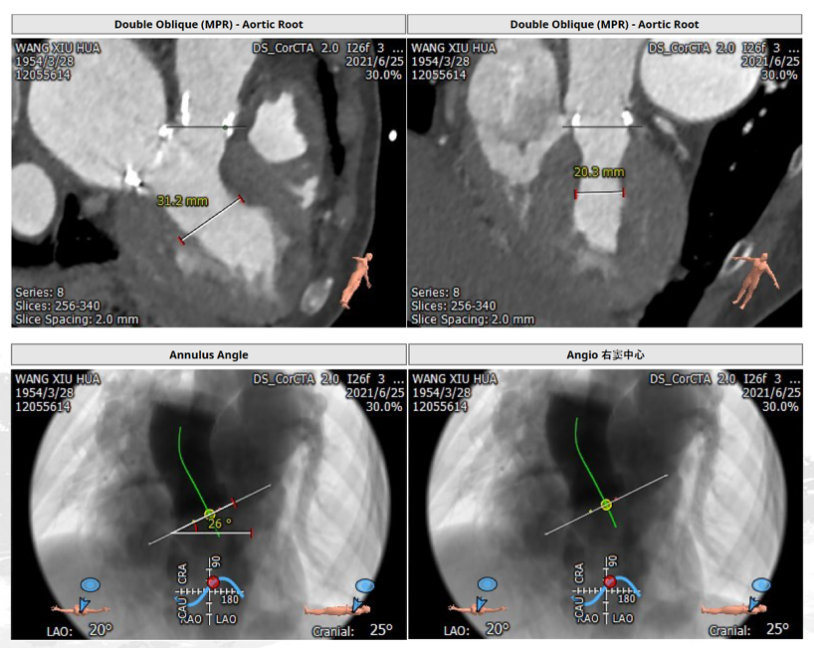

2、心室大小和投射角度评估(图2)

(二)二尖瓣位评估:

测量perimount 27瓣膜瓣环,同时评估拟植入26型号SAPIEN 3瓣膜对于左室流出道的影响,还有生物瓣投射角度分析,房间隔穿刺及距离二尖瓣生物瓣的距离分析,详细见下图(图6)。